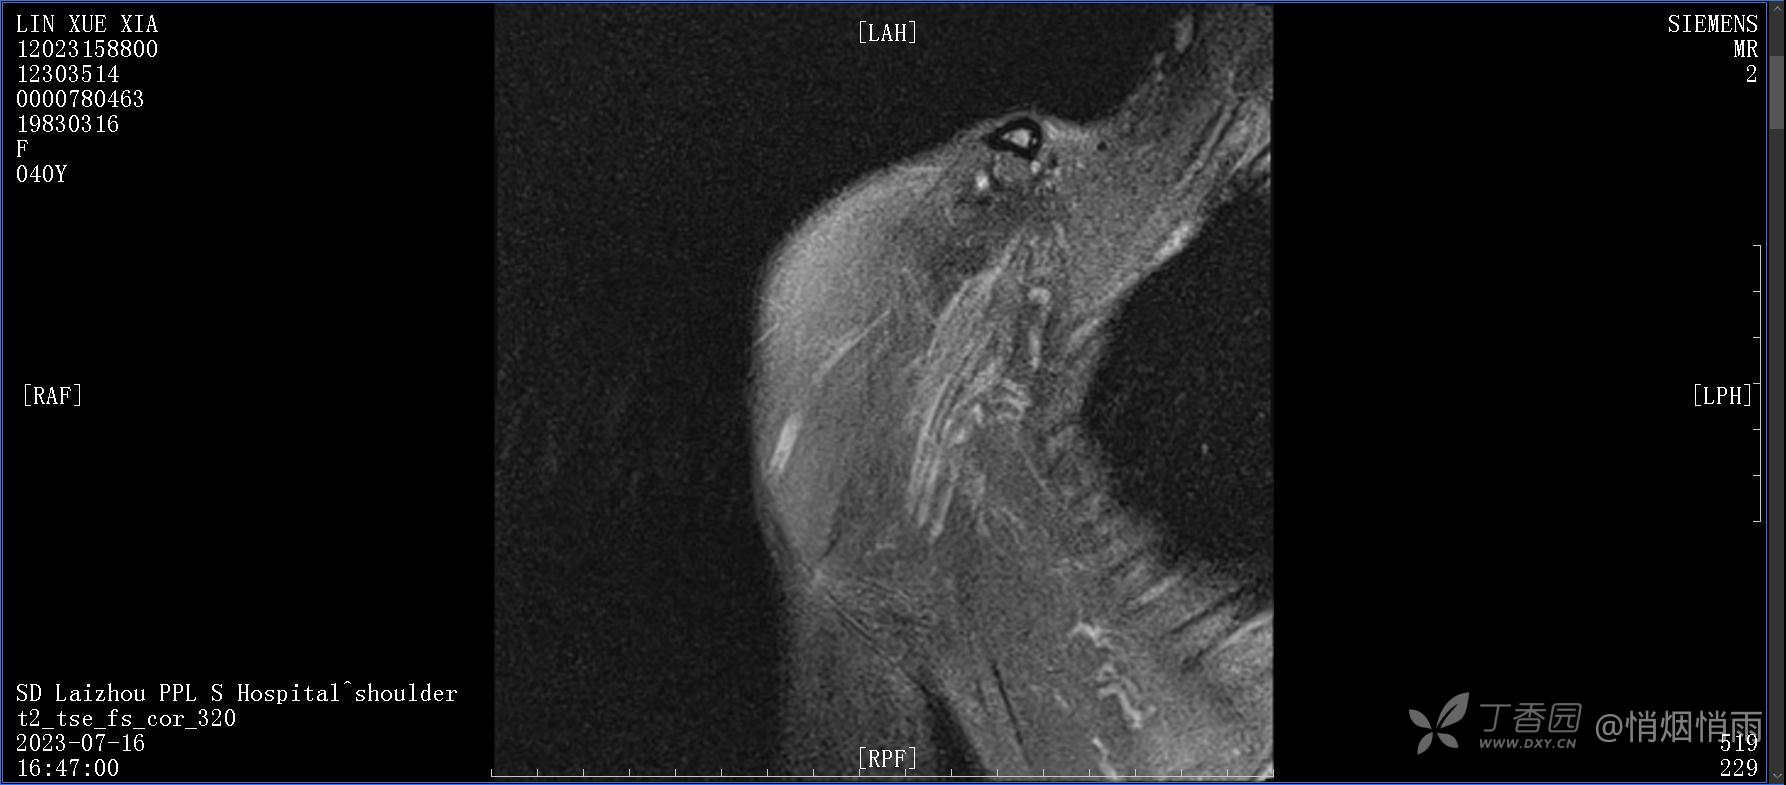

查体:右肩关节局部轻度肿胀,肩胛区压痛明显,痛处不固定,肩关节痛性活动受限,jobe test(+),lift -off test(+),中指、环指感觉较余指减退,余肢端感觉及血运情况可。

目前的诊断,暂时依据辅助检查诊为肩袖损伤,但是患者疼痛的性质和特点,却不是单纯的肩袖损伤所致。考虑过胸廓出口综合征,但是该疾病会出现肩胛区的疼痛吗?(由于考虑到费用的问题,没再进行下一步的检查)带状疱疹会有如此的症状吗?